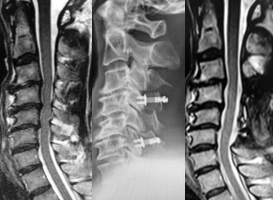

片開き式脊柱管拡大術

頚椎椎弓形成術の代表的な手術法に、片開き式脊柱管拡大術があります。ご高齢の方に対しても、安全で安定した成績が報告されている優れた術式です。手術は首の後ろを切開して、椎弓の両側に骨の溝を掘り、扉を開くように脊柱管を拡大します。開いた椎弓は再度閉じないように糸で固定したり、金属性のプレートで固定します。通常、手術翌日より座位や歩行訓練を行います。手術後のカラーは、病態により装着を考慮します。

(左)術前のMRIでは、全体的に脊柱管内の狭窄があります。(中)片開き式脊柱管拡大術を施行し、金属性のプレートで椎弓を固定しています。(右)手術により脊柱管が拡大され、神経症状が改善しています。